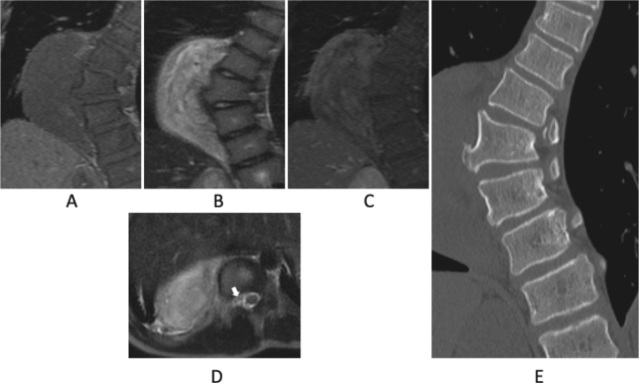

神经节神经瘤是一种罕见的良性肿瘤,起源于交感神经系统。肿瘤的表现是可变的,与青少年胸侧凸有关。在此,我们提出两个病例报告和文献综述。这两例患者分别为10岁和13岁,无肌肉疼痛或无力症状,通过影像学筛查偶然发现神经节神经瘤。两名患者都接受了两阶段的手术。第一阶段涉及肿瘤脱离脊髓,同时从后侧进行畸形矫正手术。第二阶段是通过前路切除神经节神经瘤,没有神经系统问题。两个阶段的手术是必要的切除肿瘤和纠正畸形,从而避免神经问题,同时建立病理诊断。从后路开始被证明是安全且更有效的。

Ganglioneuromas are rare benign tumors that arise from the sympathetic nervous system. The presentation of tumors is variable and associated with adolescent thoracic scoliosis. Herein, we present two case reports and a review of literature. The two cases involved 10 and 13-year-old patients who were asymptomatic for muscle pain or weakness, and ganglioneuromas were incidentally detected through imaging screening. Both patients underwent a two-stage surgery. The first stage involved detachment of the tumor from the spinal cord and simultaneously performing deformity correction surgery from the posterior aspect. The second stage was resection of the ganglioneuroma through the anterior approach without neurological problems. A two-stage surgery was necessary to excise the tumor and correct the deformity, thereby avoiding neurological problems and concurrently establish a pathological diagnosis. Commencing with the posterior approach proved to be safe and was more effective.